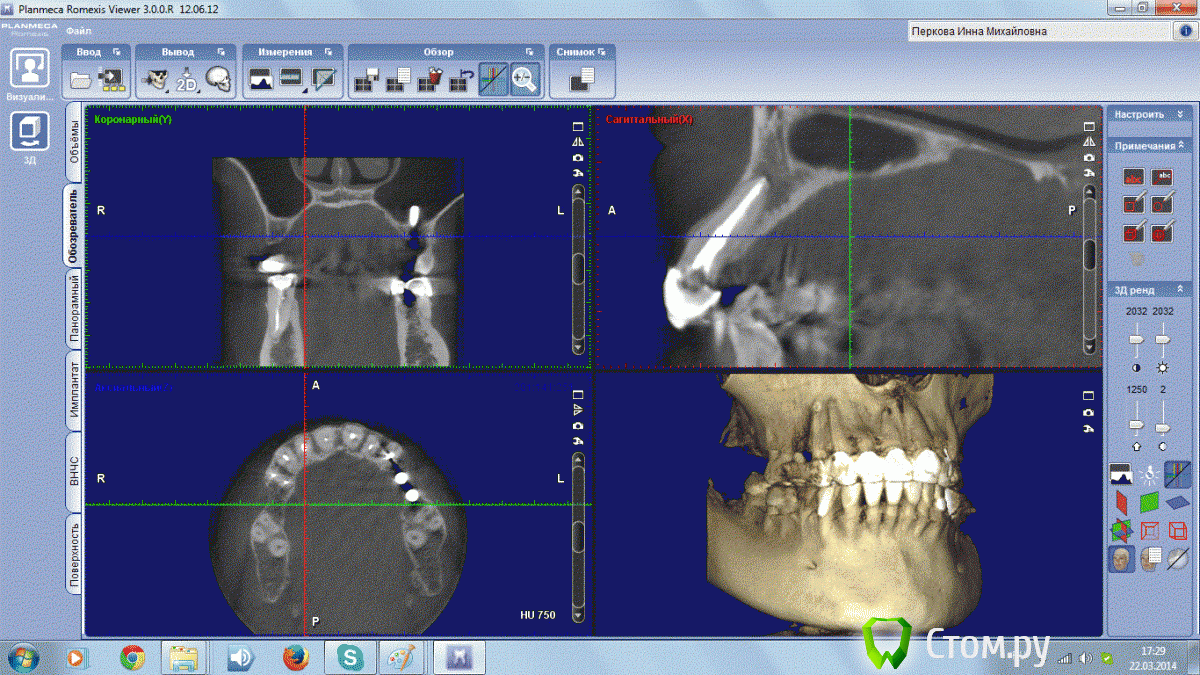

Инна Михайловна Опубликовано 22 марта, 2014 Поделиться Опубликовано 22 марта, 2014 (изменено) Добрый День!,У меня на 1 зубе обнаружили на КТ гранулему, но обнаружили уже после лечения канала. Долечен ли канал до верхушки? И посмотрите пожалуйста состояние остальных зубиков. Старая металлокерамика слетела, хочу делать новое протезирование. Изменено 22 марта, 2014 пользователем Инна Михайловна Ссылка на комментарий

Гарриевич Опубликовано 23 марта, 2014 Поделиться Опубликовано 23 марта, 2014 Там где слетела старая керамика, зубы лечите и протезируйте Ссылка на комментарий